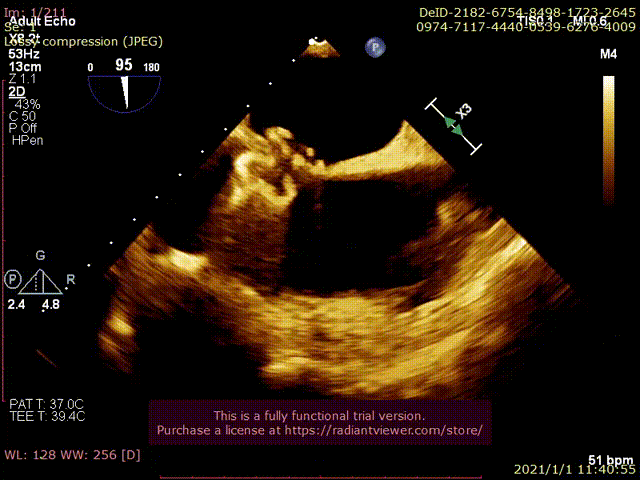

术中分流器形态稳定

食道超声可见左向右分流束